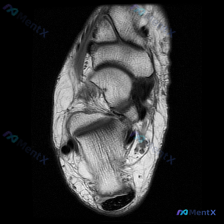

刚看到一个很有讨论价值的踝关节MRI读片病例,整理了一下资料和分析思路,跟大家分享。 病例影像基础信息 这是踝关节MRI-T2序列矢状位图像,核心问题是“影像中可以看到什么?提示软组织积液”。 先给大家整理影像所见: 1. 骨性结构:胫骨远端、距骨、跟骨、舟骨等结构显示清晰,骨髓信号整体正常,未见明...

最近看到一份踝关节MRI读片请求,问题是「影像中能观察到什么?提示软组织积液」,整理了完整的读片和分析思路,和大家分享讨论。 一、影像基本信息 这是踝关节矢状位MRI T2序列,影像观察结果如下: 1. 骨结构:胫骨远端、距骨、跟骨、舟骨、部分楔骨骨皮质轮廓完整,胫距关节间隙可见 2. 关节腔:胫距...

看到这个踝关节MRI的读片请求,问题是观察到的软组织积液,我整理了完整的影像和分析思路分享给大家。 病例影像基础信息 这是踝关节MRI矢状位T2序列图像,核心观察结果如下: 1. 骨骼系统:胫骨远端、距骨、跟骨、舟骨骨皮质完整,未见明确骨折线;距骨体及跟骨骨髓信号均匀,无明显水肿或硬化改变 2. 关...

今天给大家分享一张踝关节MRI矢状位T2加权影像的读片分析,病例本身并不复杂,但这种仅表现为少量积液的情况,临床其实很容易走偏,整理一下完整的思考过程给大家参考。 一、影像核心信息整理 这张是踝关节矢状位T2加权MRI,我们先把所有明确的影像信息理清楚: 1. 骨骼结构:胫骨远端、距骨、跟骨、舟骨骨...